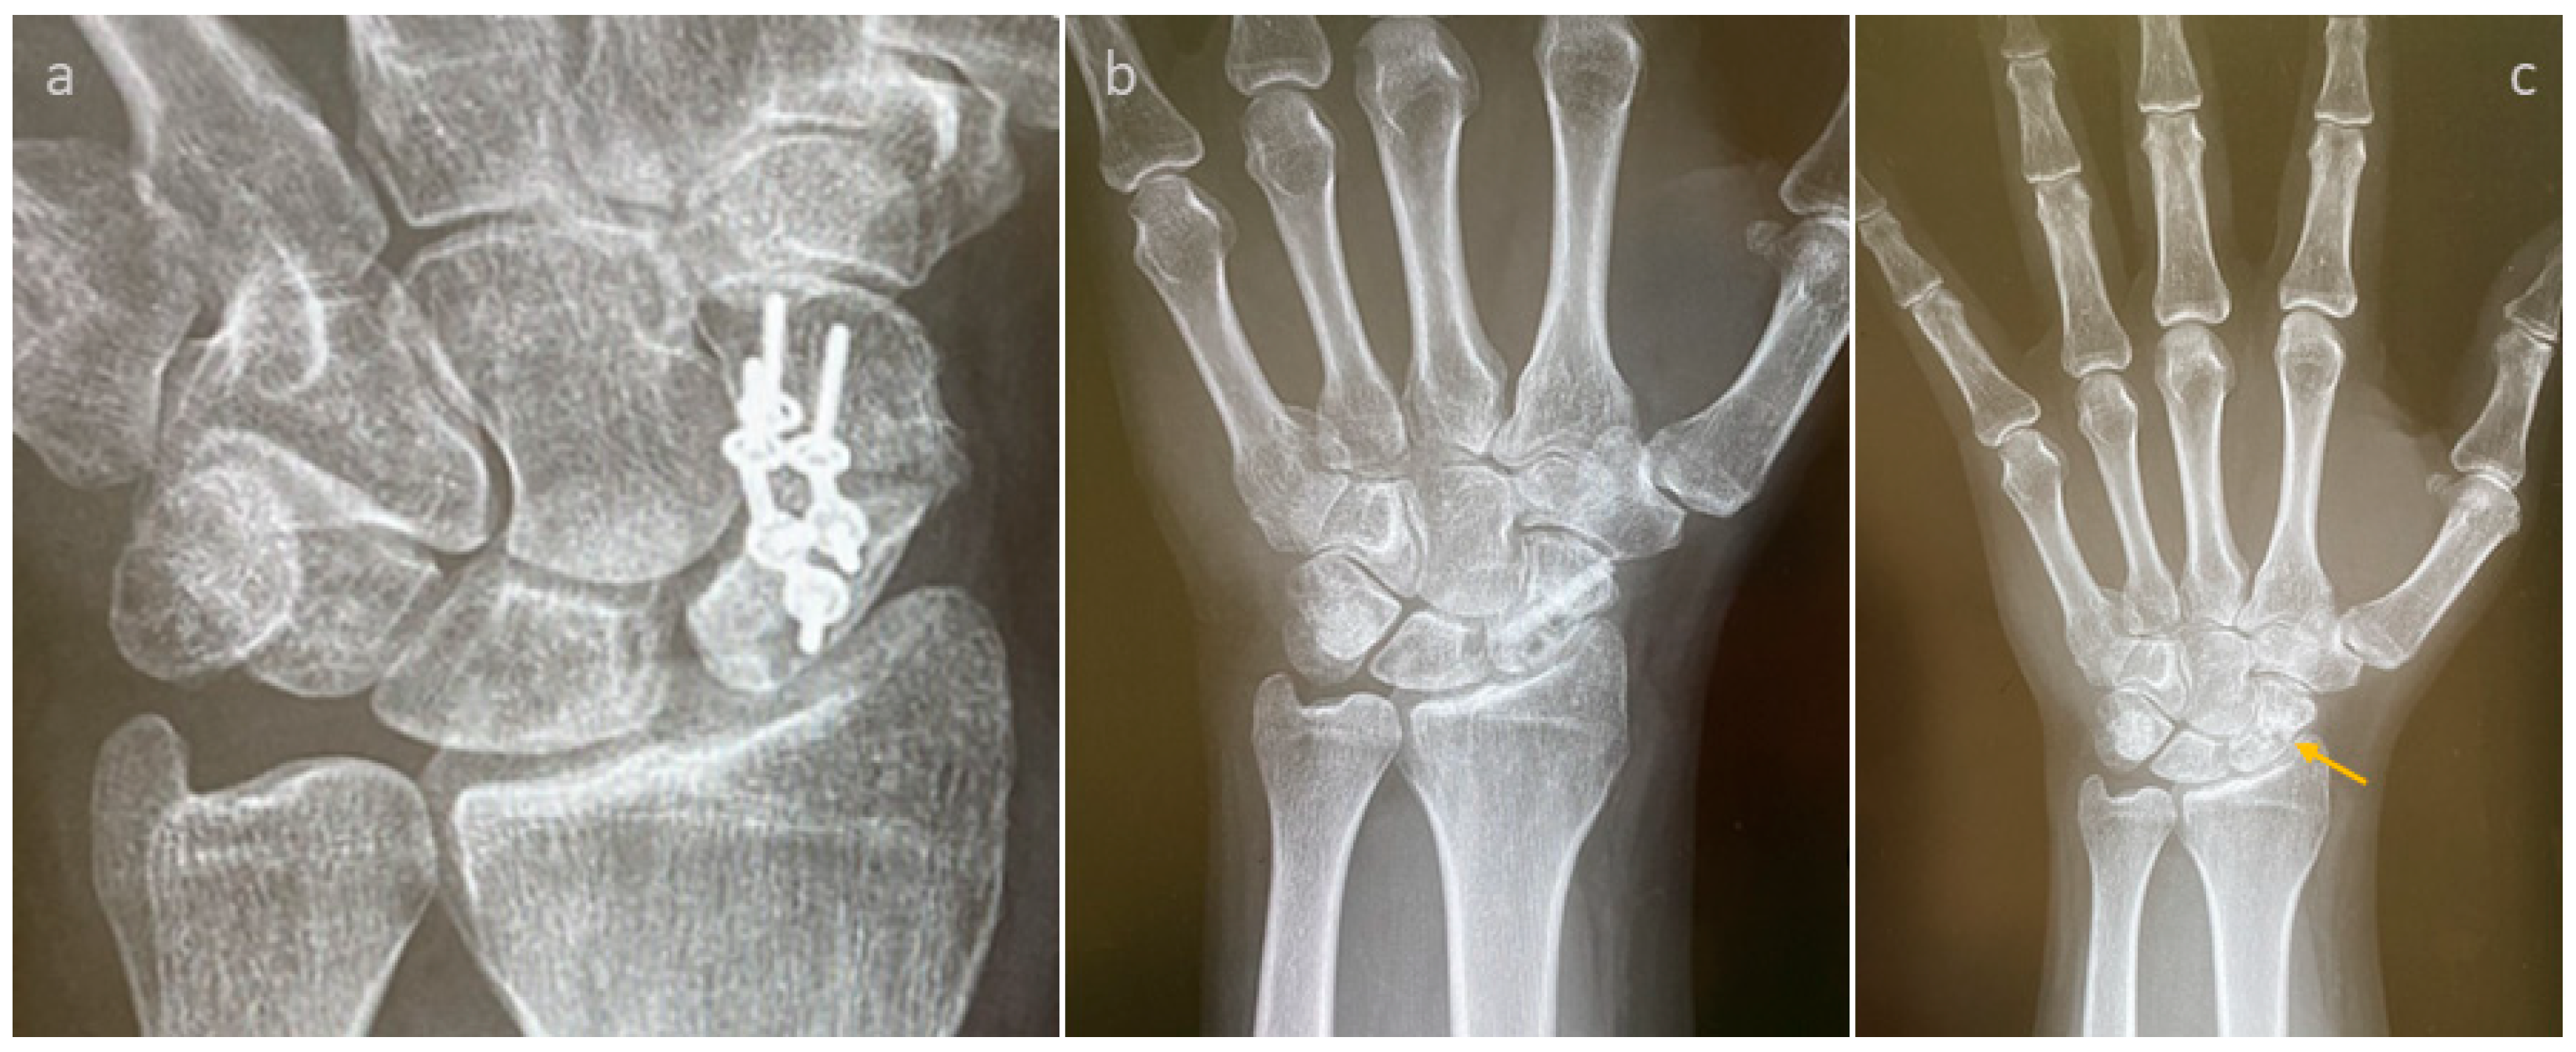

3.4. Selected Case Descriptions